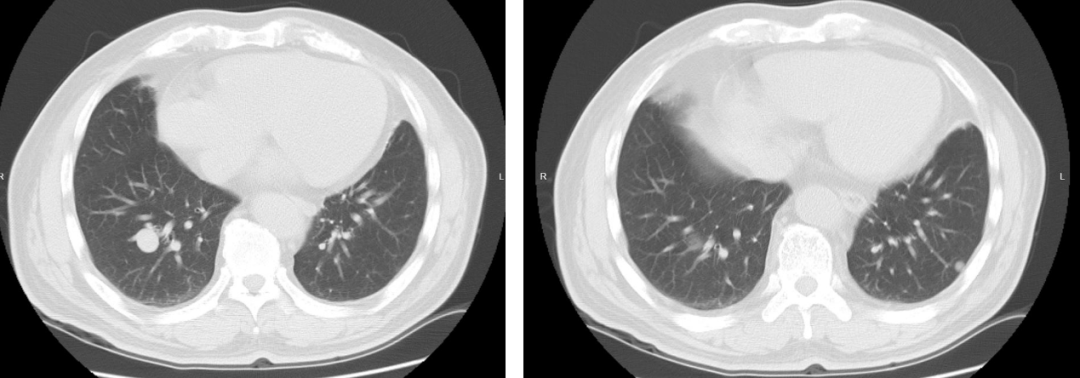

图1 患者基线胸部影像学图像(2024年4月16日)

ECT骨扫描未见骨转移;B超提示未见肝转移灶;头颅MRI提示未见脑转移

右肺穿刺病理:(肺结节穿刺标本)结合免疫组化及病史,符合肾透明细胞癌肺转移

免疫组化:TTF-1(-)、NapsinA(-)、CAIX(+)、PAX-8(+)